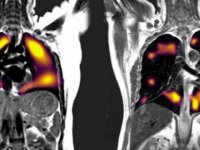

Salgın sürecinde acil sağlık hizmetleri kapsamında taşınan hasta sayısı arttıYeni tip koronavirüs salgını ile mücadele sürecinde 112 acil sağlık ekiplerinin kara, hava, deniz yoluyla taşıdıkları hasta sayısı arttı.02 Aralık 2020 Çarşamba 11:44 Corona Virüsü Akciğerleri Böyle Etkiliyorİngiltere'de geliştirilen yeni bir manyetik görüntüleme tekniği ile, Covid-19 teşhisi konan hastaların akciğerlerinde teşhisten üç ay sonra bile bazı anormallikler tespit edildi.02 Aralık 2020 Çarşamba 11:41

Corona Virüsü Akciğerleri Böyle Etkiliyorİngiltere'de geliştirilen yeni bir manyetik görüntüleme tekniği ile, Covid-19 teşhisi konan hastaların akciğerlerinde teşhisten üç ay sonra bile bazı anormallikler tespit edildi.02 Aralık 2020 Çarşamba 11:41 Coşkun: Dipkarpaz Bunu Da AtlattıDipkarpaz Belediye Başkanı Suphi Coşkun, geçen hafta Karpaz'da görülen Covid-19 vakalarının ardından tarama testlerinin devam ettiğini belirtti01 Aralık 2020 Salı 15:08